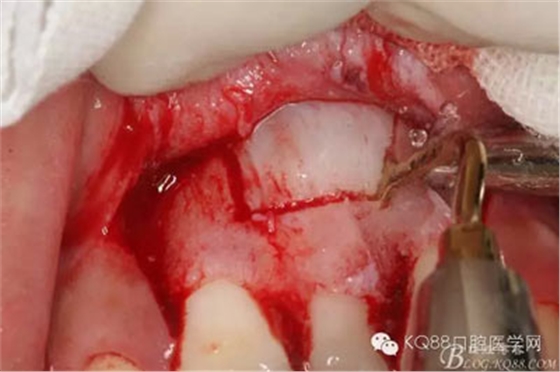

圖12.摘除囊壁后,暴露出21的切端

圖13.超聲骨刀清理周圍組織,21有Ⅰ°松動

圖14.牙冠周圍滲血多,無法粘結(jié)托槽。位置也高,隨與家屬溝通,暫時保留乳Ⅰ。待21初步穩(wěn)定,再考慮正畸牽引